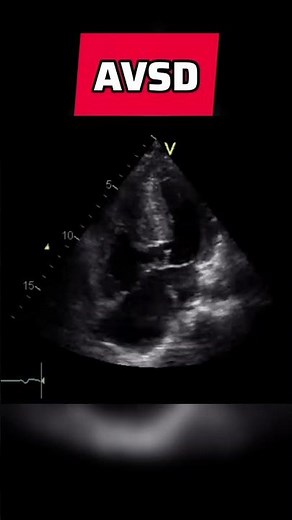

Atrioventricular septal defect - congenital heart defect #echocardiography #AVSD

YouTube

Dr. M Usman Javed

15.2K views

Jun 20, 2024

Atrioventricular septal defect - congenital heart defect #echocard

…